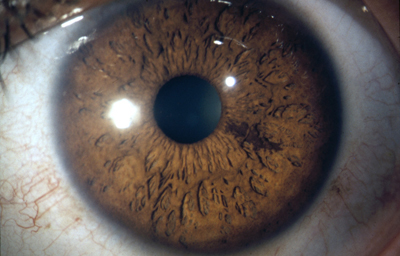

En la cara Anterior esta el pigmento que le da el color al Iris y dependiendo del grado de reabsorción u atrofia de esa capa anterior se pueden observar:

Las Criptas de Fuchs: que son pequeñas aberturas alrededor del collarete, producto de la atrofia o reabsorción de la hoja anterior del iris, que le permiten al estroma y a los tejidos mas profundos estar en contacto con el humor acuoso.

La vascularización proviene de las arterias ciliares largas y las ciliares anteriores, que penetran formando una malla radial en el estroma iridiano.

Existe el círculo vascular mayor del Iris situado en la periferia que ya es estroma del cuerpo ciliar, y el círculo menor en el collarete.